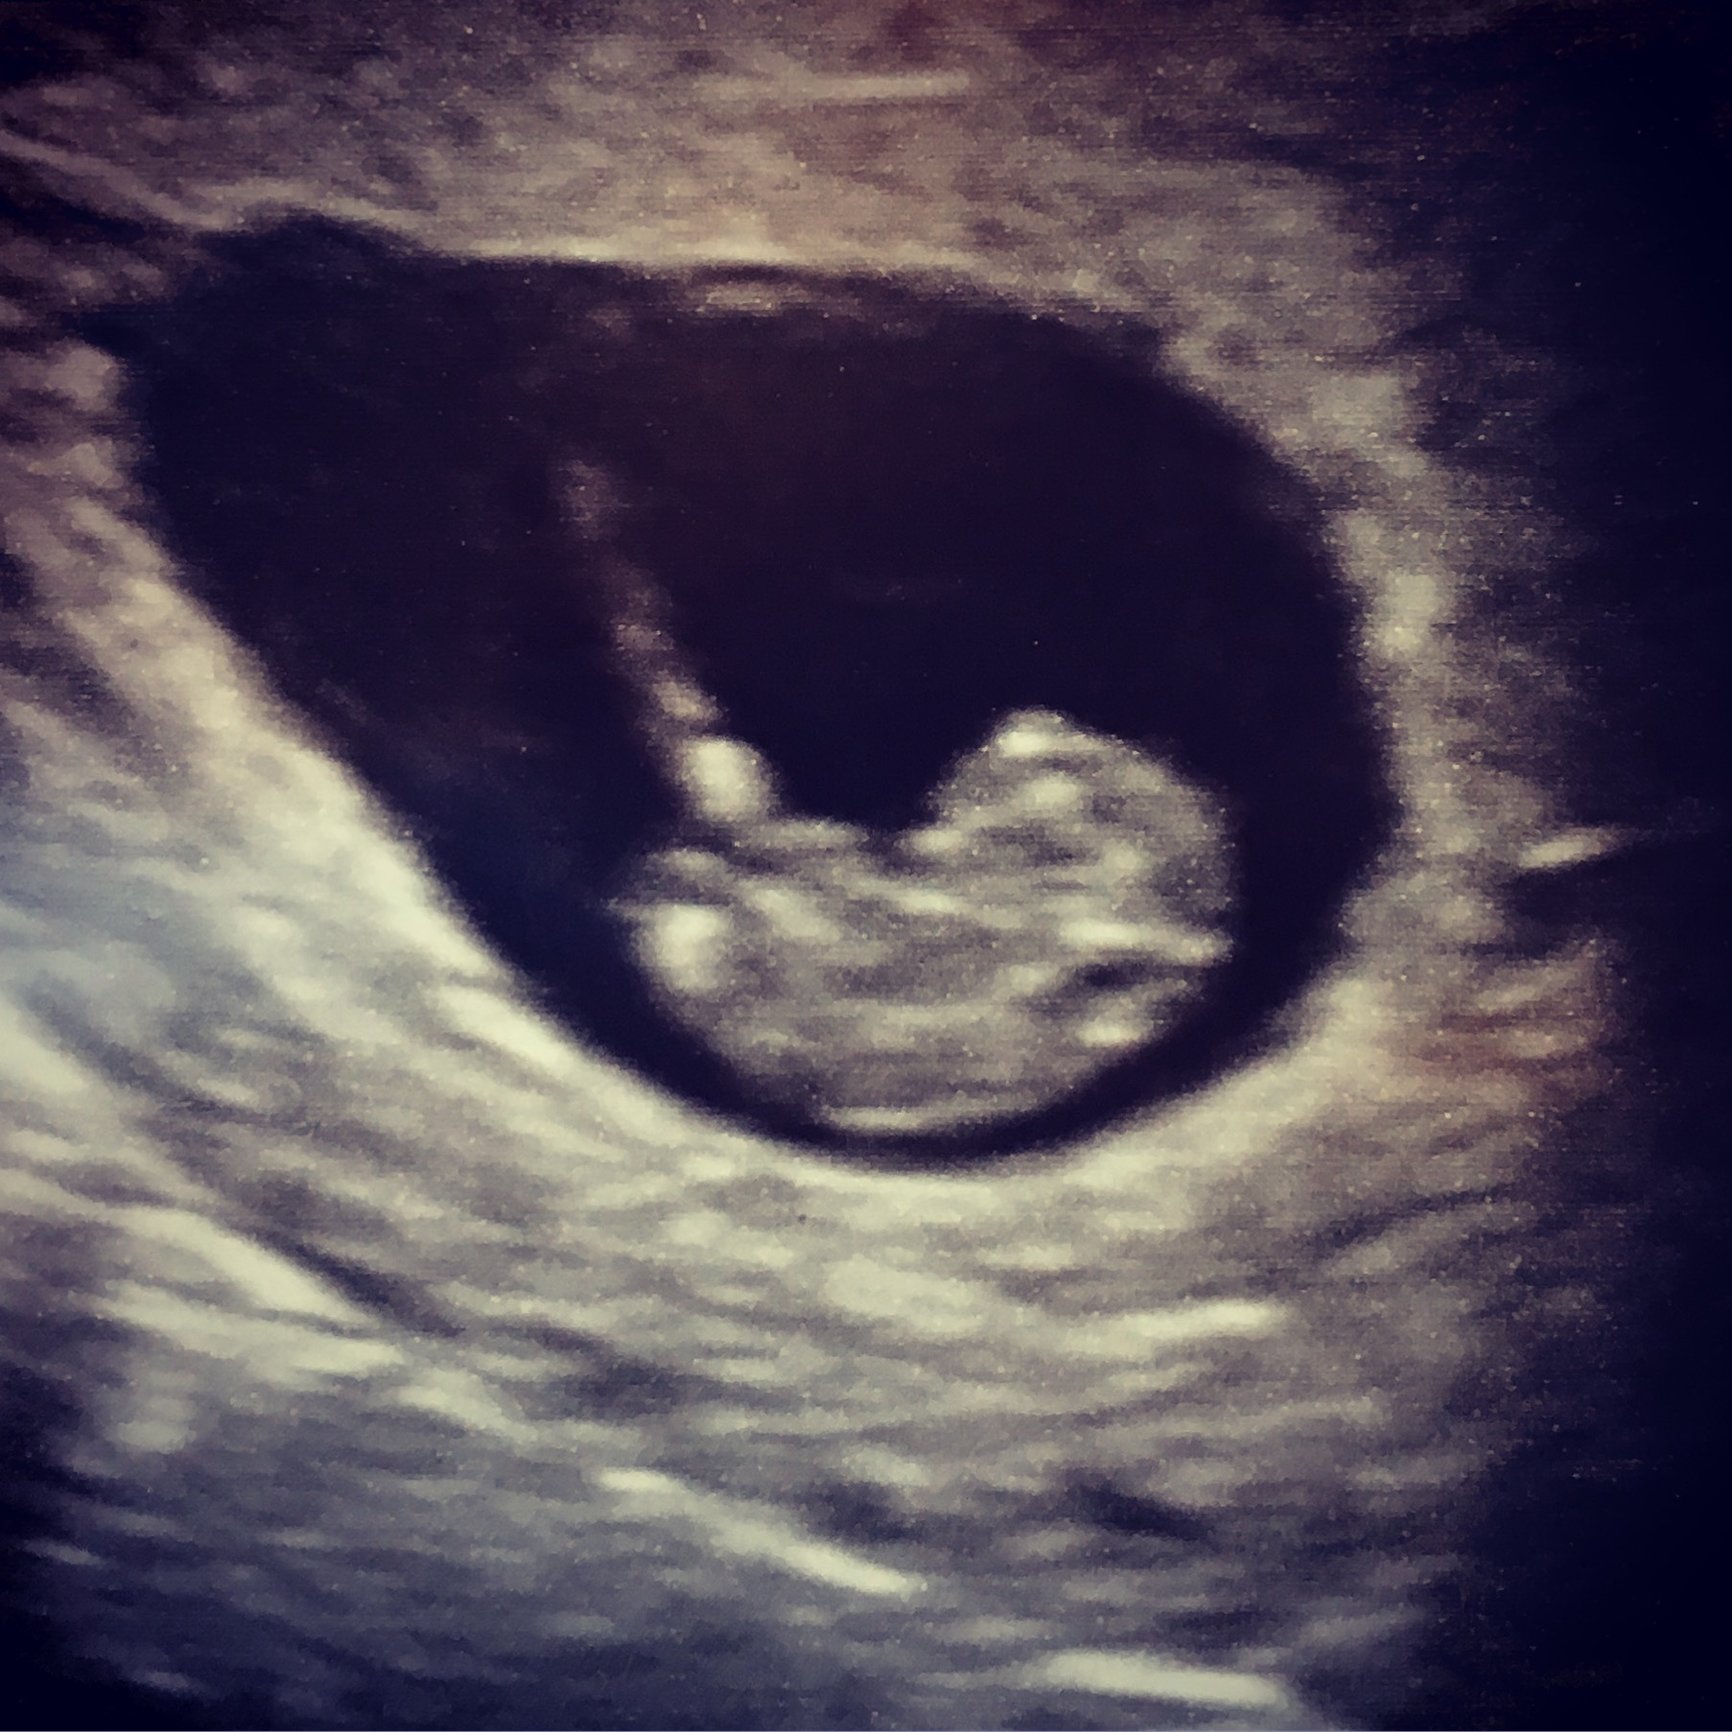

i was told that I am 8 weeks and 3 days and this was my picture. Where is the placenta located? This was done transvaginal so I heard things are flipped?

Wait, why would you want to know where the placenta is? I mean, I’m all about knowing as much about what’s going on as possible, but is this another sex guessing game thing?

• @ceridwen77 yes, it's another guessing thing- the ramzi method. I had never even heard of this with my prior pregnancies, so I don't imagine it's backed by years of science and rigorous testing.